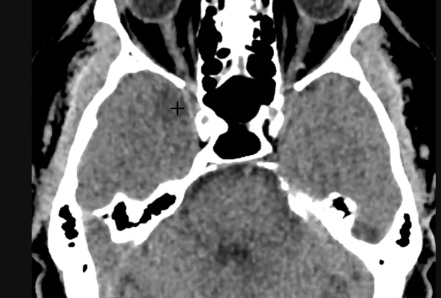

Encéphalite Herpétique (HSV)

- Une des plus fréquentes

- Immunocompétent = Atteinte bilatéral temporale médiale + système limbique

- Immunosupprimé = Atteinte diffuse

- Diagnostic par ponction lombaire (avec PCR)

- Forme infantile différente

- DD: Encéphalite Limbique (patients plus agés, paranéoplsique++)